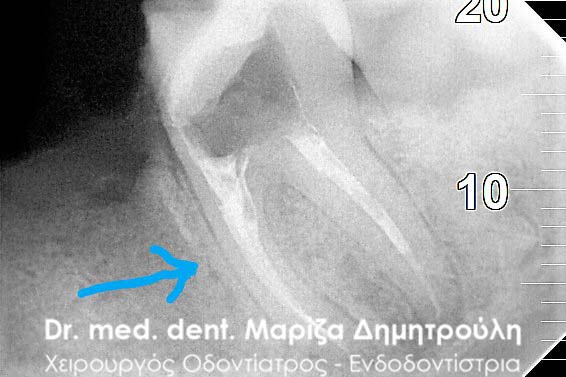

Πριν 2 χρόνια είχε πραγματοποιηθεί απονεύρωση στον πρώτο αριστερό μόνιμο γομφίο (τραπεζίτη). Ο ασθενής αναφέρει οτι από τότε που ξεκίνησε η ενδοδοντική θεραπεία, το δόντι δεν έπαψε ποτέ να πονάει.

Αρχικα ο ασθενής εξετάστηκε κλινικά και παρατηρήθηκε έντονος πόνος κατά την επίκρουση του δοντιού. Ακολούθησε ο ακτινογραφικός έλεγχος, ο οποίος εξήγησε και τα συμπτώματα πόνου του δοντιού. Διαπιστώθηκε οτι μόνο μία από τις τρείς ρίζες του δοντιού είχε εμφρακτικό υλικό. Η δεύτερη φαινόταν κενή, ενώ στην τρίτη διέκρινε κανείς μόνο την παρουσία κάποιου φυράματος.

Μετά την πλήρη ενημέρωση του ασθενή αποφασίστηκε η επανάληψη της ενδοδοντικής θεραπείας (απονέυρωσης) και η αποκατάσταση του δοντιού με καινούριο λευκό σφράγισμα.

Εφόσον η ασθενής δεν πονούσε και το δόντι ήταν ασυμπτωματικό, ακολούθησε η ολοκλήρωση της απονεύρωσης με της έμφραξη των ριζών του δοντιού. Σε επόμενο ραντεβού το δόντι αποκαταστάθηκε με λευκό σφράγισμα.